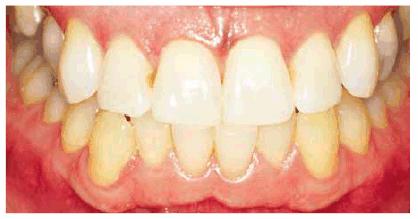

either on an individual tooth or on all teeth (Figures 16-1A, and 16-1B). There are many causes and

Figure 16-1A: An otherwise attractive smile is marred by discolored teeth.

Figure 16-1B: After tooth lightening, the smile is much more pleasing.